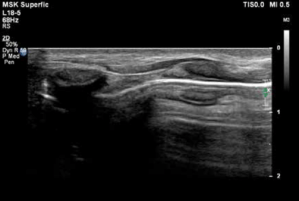

ECO